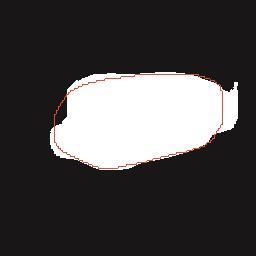

乳腺癌是全球女性最常见的恶性肿瘤之一,准确的病变分割对于乳腺癌的早期诊断与治疗具有重要意义。然而,由于病变形态的多样性以及超声成像机制的复杂性,现有基于深度学习的乳腺超声图像病变分割方法在分割准确性方面仍面临巨大挑战。为进一步提升乳腺超声图像中病变区域的分割精度,该文基于经典U-Net架构,提出了一种新型乳腺超声图像病变分割网络(CWSASKM-BBAM-Net)。首先,在网络中引入逐通道空间自适应选择核卷积模块(CWSASKM),根据不同通道的语义特征为每个空间位置自适应选择感受野大小,以增强多尺度信息的建模能力;然后,引入双向边界感知机制(BBAM),通过融合正向与反向注意力,对目标显著区域及其边界进行协同建模,同时逐步提升对非显著区域与病变区域的区分能力,以进一步强化边界信息的表达;最后,在3组公开乳腺超声图像数据集(BUSI、UDIAT和STU)上开展分割实验。结果表明:该方法在数据集BUSI上的杰卡德指数、精确率、召回率和Dice相似系数分别为71.97%、82.85%、81.40%和80.44%,较次优方法分别提升1.69、1.05、1.28和1.84个百分点;在数据集UDIAT上,这4项指标分别达到78.14%、88.31%、86.73%和86.10%,较次优方法分别提升了2.75、2.04、0.56和2.01个百分点;在外部数据集STU上,该方法也取得了优于其他方法的整体表现。实验结果表明,CWSASKM-BBAM-Net在乳腺超声图像分割任务中展现出更优的整体性能。